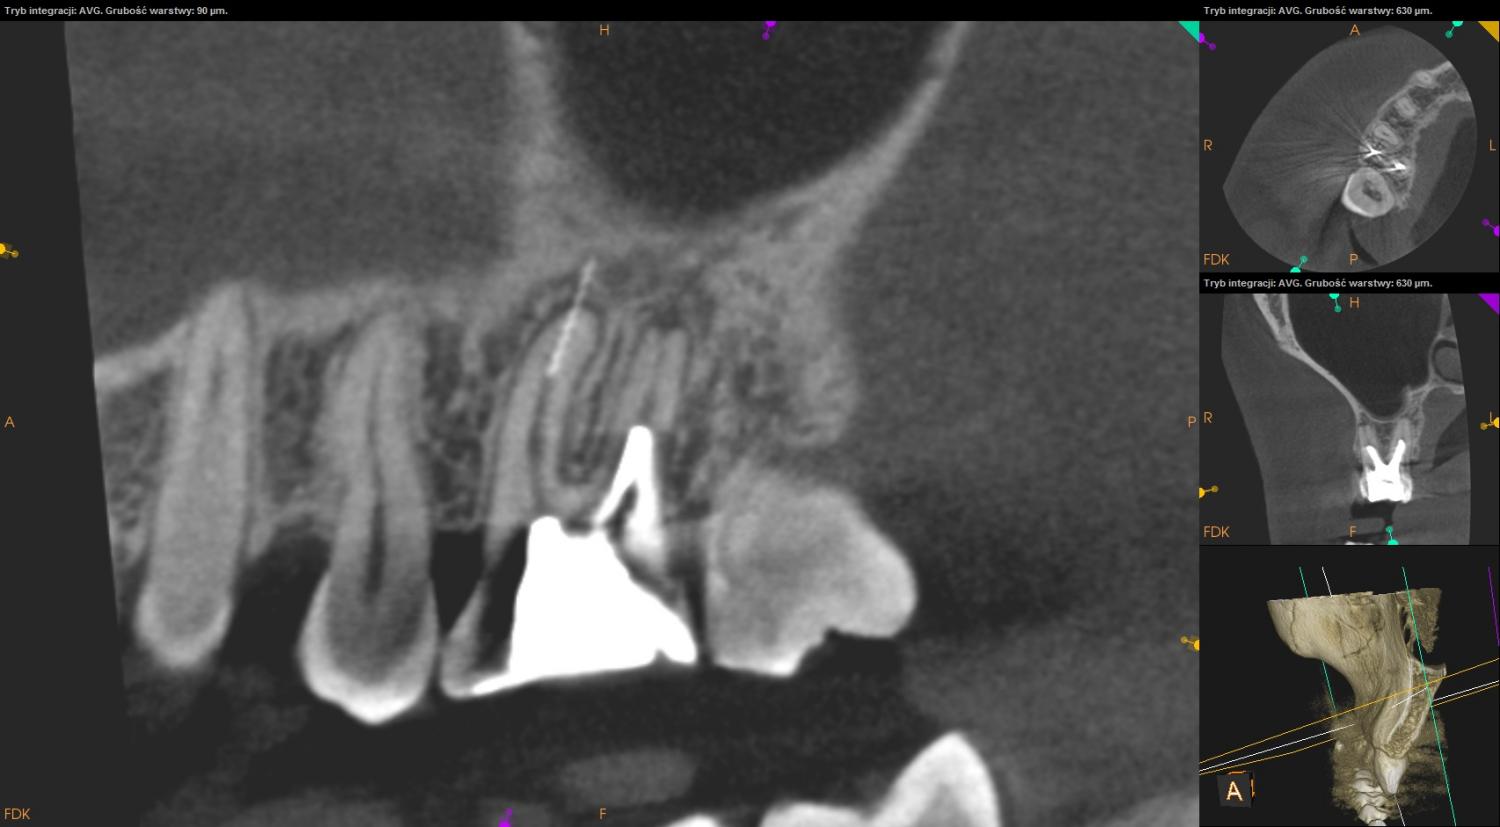

Tomografia szczęka, okolica 16.

Ząb 16 – posiada znamiona leczenia kanałowego. W kanałach dystalnym i podniebiennym umieszczone wkłady. Powyżej wkładów, w części przywierzchołkowej kanałów materiał wypełniający niewidoczny (kanał dystalny – 4mm, podniebienny – 4,5mm). Widoczne cztery światła kanałów. Kanały mezialne niewypełnione. W kanale mezialnym w okolicy wierzchołka widoczne złamane narzędzie endodontyczne. Szpara ozębnej wokół wierzchołków korzeni poszerzona.